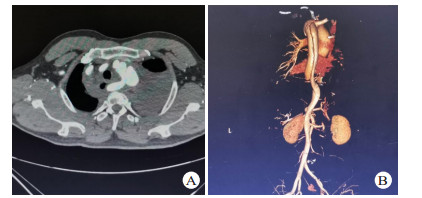

1.3 手术方法除1例主动脉夹层患者合并严重骨盆骨折及全身多处器官损伤,因失血性休克于入院后3 h死亡,其余13例患者均在全麻或局麻下行TEVAR。所有患者均在入院后48 h内完成TEVAR。TEVAR在数字减影血管造影(digital substraction antiography,DSA)室进行,转流手术及其他脏器手术在手术室进行。11例患者采用全身麻醉,2例采用局部麻醉。手术切口均腹股沟切口进行。患者取仰卧位,两侧腹股沟区充分消毒,铺无菌巾,经腹股沟切口暴露股动脉,Seldinger方法穿刺股动脉,置入5 F导管鞘,插入标记导管,将导管置于膈肌平面,注入造影剂,了解主动脉有无其他破口及腹腔重要血管分支供血情况,最后将导管尖端置于升主动脉,行正位及45°左前斜位行主动脉造影,明确主动脉破口位置及真假腔情况(图 2A),测量锚定区主动脉直径,选择合适大小的覆膜支架,进超硬导丝,取出导管及导管鞘,将支架系统输送至锚定区,定位准确后释放覆膜支架,再次造影明确夹层破口覆盖情况(图 2B),左侧锁骨下动脉供血情况,及有无内漏等。合并血胸患者行TEVAR后在介入室立即行胸腔闭式引流,并控制引流速度及引流量。伴有其他合并伤需手术的患者在进行TEVAR后转至手术室行合并伤手术; 同期脾切除、肠穿孔修补、剖胸探查止血各1例,TEVAR后2周后行骨折内固定术2例。术后所有患者均返回本重症监护室进行进一步治疗。

| 图 2 患者23岁,因高处坠落伤入院,入院后诊断TAD,破口大,急诊行TEVAR(A:术中主动脉造影显示破口位于降主动脉峡部,靠近左侧锁骨下动脉,真腔小,假腔大; B:术中再次主动脉造影,夹层破口封闭满意,无内漏) |